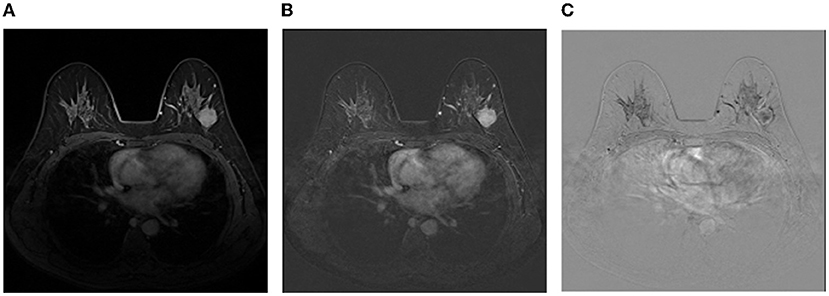

Image representation: Although irrelevant regions can be excluded by breast masks predicted by the trained DenseUNet, there are still a lot of negative regions, leading to a serious class-imbalance problem. Thus, images are cropped to reduce negative regions and more details can be found in the experimental section. Then, we employ the image representation as the same as Amit et al. (2017) for the cropped regions of DCE images, where a multi-channel sample is constructed to capture anatomical and metabolic characteristics. Figure 3 shows an illustration of the 3-channel image representation, where Ibase denotes the pre-contrast T1 image, Ipeak is the image at peak enhancement, Iearly is the initial response image after contrast injection, and Idelayed is the delayed enhancement which is usually the last acquired temporal series. All the 4 series are raw images exported from the same MRI scanner directly. Hence, the first channel is Ipeak, the second channel is the T1-subtracted image at peak enhancement Ipeak-Ibase, and the last channel is the contrast washout image Iearly-Idelayed.

Figure 3. An illustration of the image representation with three channels. (A) The first channel:Ipeak; (B) The second channel:Ipeak-Ibase; (C) The third channel:Iearly-Idelayed.